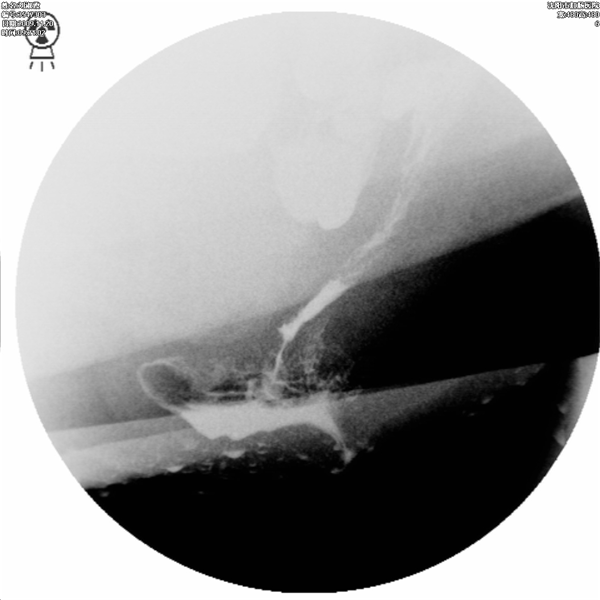

排便造影就是将钡剂模拟粪便灌入直肠内,患者坐在易透X光的排便器上,在患者排便的过程中,多次摄片或录像,以观察肛管、直肠的影像学改变,动态观察钡剂排出(模拟排便)过程中肛门和直肠的功能变化。排便造影能为会阴下降、直肠前突、直肠前壁粘膜脱垂、内套叠、盆底疝、内脏下垂、耻骨直肠肌肥厚等疾病的诊断及鉴别诊断提供可靠的依据.

直肠前突合并会阴下降

直肠前突合并直肠前壁粘膜脱垂